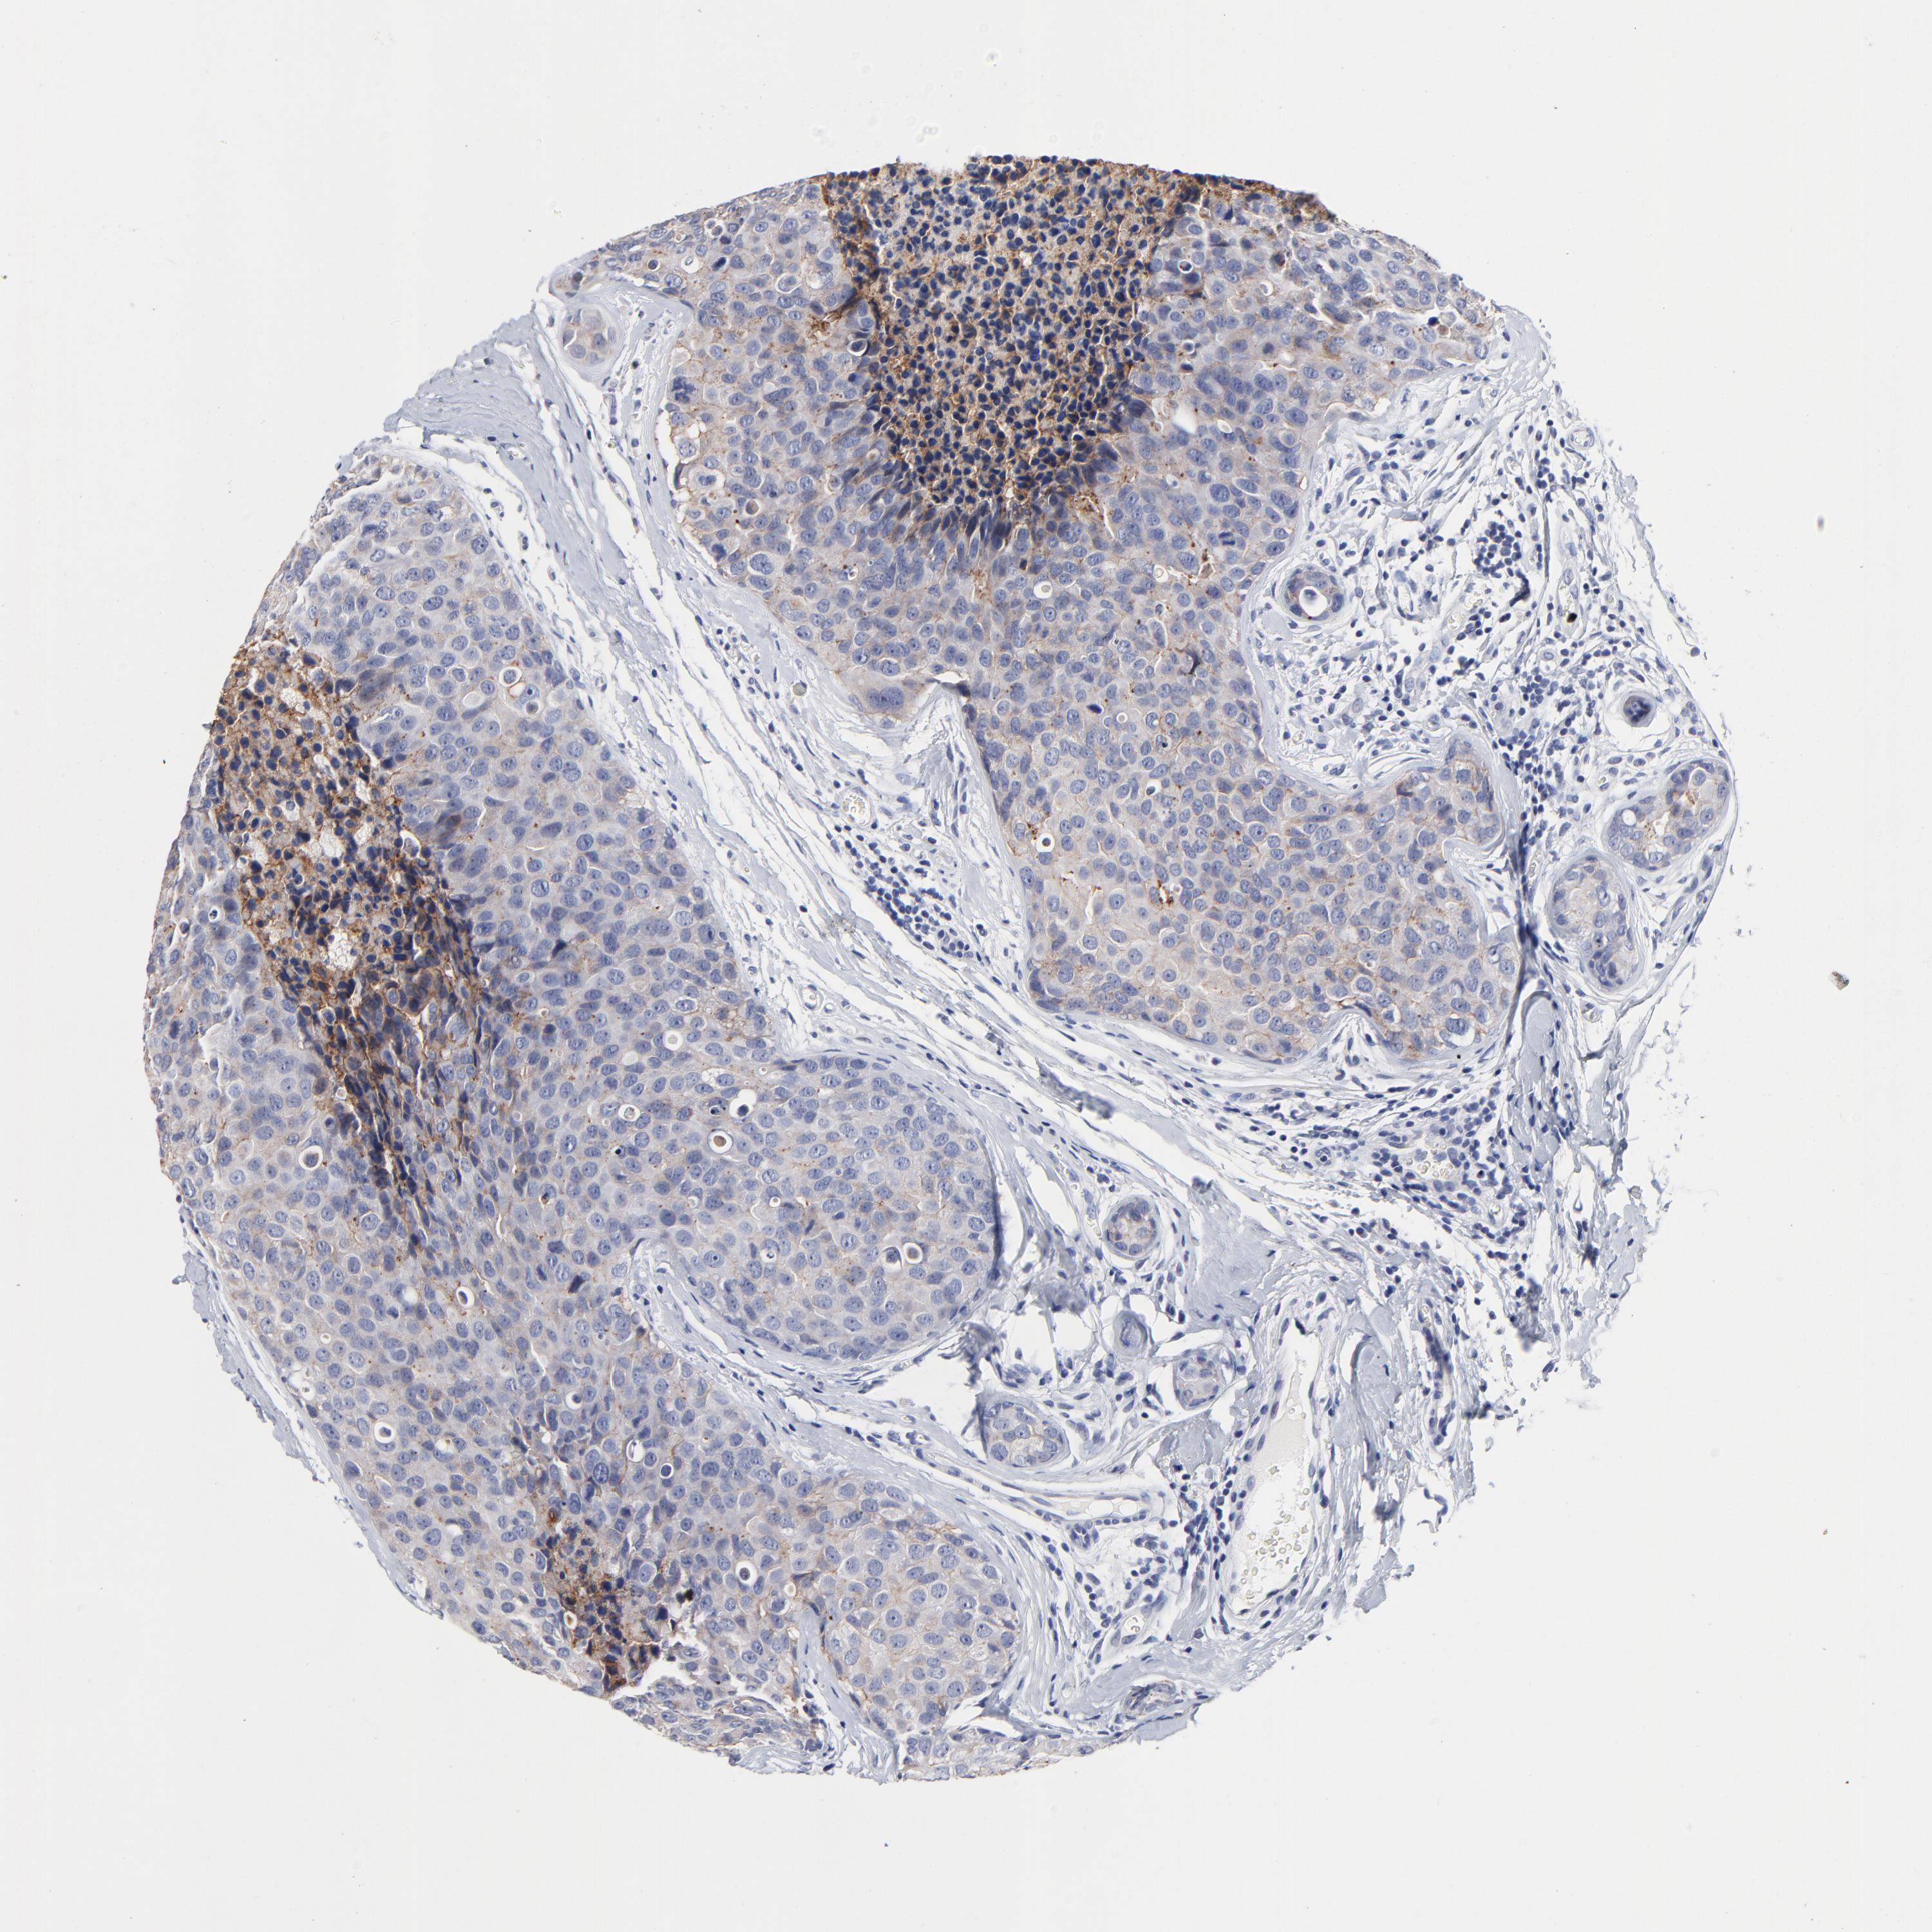

CANCER BREAST CANCER Show tissue menu

BRCA TCGA BRCA VALIDATION PROTEIN EXPRESSION

ANTIBODIES

AND

VALIDATION